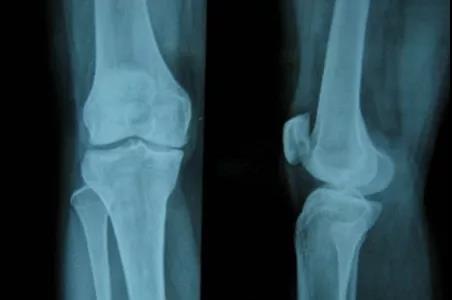

菌性炎症是痛苦、晨僵的元凶巨恶,而关节粘连是患者受限、抬臂下蹲困难的首要原因,免疫紊乱是病况发作的本源,而传统血液、CT检查只能检查有无炎症,却不知道炎症详细分布与多少,对关节囊炎症包裹程度与关节腔炎性粘连认识不清,且传统血常规检查只知免疫是否紊乱,无法检测免疫紊乱详细原因,一旦触发诱发因素,病况难逃反复。

3、骨质受损、关节活动受限

随着类风湿病况发展,患者最明显的感觉就是关节像胶水粘住一般僵硬,抬臂、弯腰下蹲,这是因炎症堆积,滑膜增生增厚,导致软安排出现粘连,骨质钙化或交融所致。这些症状想要改善,就必须及时把粘连的关节,以及关节周围的肌肉和韧带松解开,而患者选择的药物、打针等医治方式虽然能够缓解关节部位的痛苦,但是无法做到对粘连安排进行松解的作用。